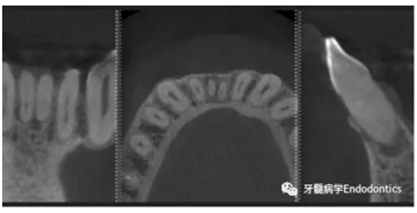

31、41叩痛明顯,牙冠變色(圖1)。溫度和牙髓電活力測(cè)試無反應(yīng)。兩張從不同角度拍攝的x線片顯示,相對(duì)于側(cè)切牙,雙側(cè)下中切牙都有嚴(yán)重的根管鈣化(圖2)。41有明顯根尖周暗影,31根尖周暗影不明顯。為進(jìn)一步證實(shí)31是否存在根尖周病變,同時(shí)精細(xì)觀察31、41的復(fù)雜結(jié)構(gòu),根據(jù)歐洲牙髓病學(xué)會(huì)CBCT應(yīng)用指南(2014),對(duì)患牙拍攝小視野、高分辨率CBCT。CBCT影像證實(shí)31、41均伴有根尖周炎和嚴(yán)重的根管鈣化(圖3)。距離根尖4mm可見根管影像。 由于患牙根管解剖結(jié)構(gòu)較為復(fù)雜,筆者決定使用特殊設(shè)計(jì)的微型鉆頭(直徑0.85mm)進(jìn)行“數(shù)字化導(dǎo)航牙髓治療”。 因此對(duì)下頜進(jìn)行口內(nèi)掃描(圖4)。用coDiagnostixTM軟件(Dental Wings Inc.,Montreal,Canada)將CBCT和口內(nèi)掃描的數(shù)據(jù)進(jìn)行處理,該軟件主要用于引導(dǎo)種植。通過該軟件對(duì)兩個(gè)掃描圖像進(jìn)行疊加后,虛擬鉆頭尖端沿牙長(zhǎng)軸對(duì)準(zhǔn)根管下段可見部分(圖5)。三維檢查虛擬鉆的正確位置。

圖3.下頜前牙CBCT影像。